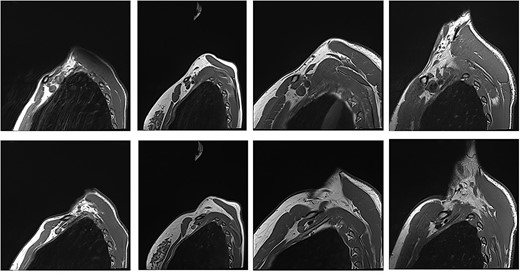

With the arm elevated, there is narrowing of the costoclavicular space between the posterior border of the clavicle and anterior border of the first rib (Figs 1 and 3). In unaffected patients, there is a small amount of fat that persists around the cords of the brachial plexus with the arm elevated (Fig. 2). In our series, we considered a patient to be positive for nTOS if there is loss of the perineural fat signal demonstrating that the nerves are in direct contact with the posterior border of the clavicle and anterior border of the first rib (Fig. 1b).

Unaffected patients. The top row are sequences with the arm in the neutral position. The bottom row is the corresponding patient with the arm raised.